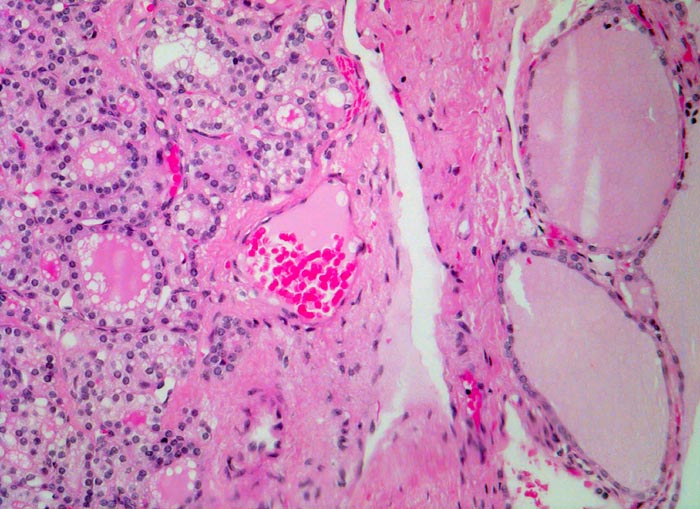

• Anschnitt eines grossen mikrofollikulären Knotens (autonomes Adenom) mit angedeuteter Kapsel und zentraler Einblutung. Oben zwei weitere kleine Satellitenknoten.

• Kompression des angrenzenden Schilddrüsenparenchyms. Dieses besteht aus grossen Follikeln mit kubischem oder abgeflachtem Epithel und reichlich kompaktem dunklem Kolloid in den Follikellumina.

• Zeichen gesteigerter hormoneller Aktivität im Adenom:

• Kleine Drüsenlumina.

• Teils mehrreihiges kubisches bis zylindrisches Epithel.

• Fehlendes oder nur spärliches helles Kolloid mit zahlreichen Resorptionsvakuolen.